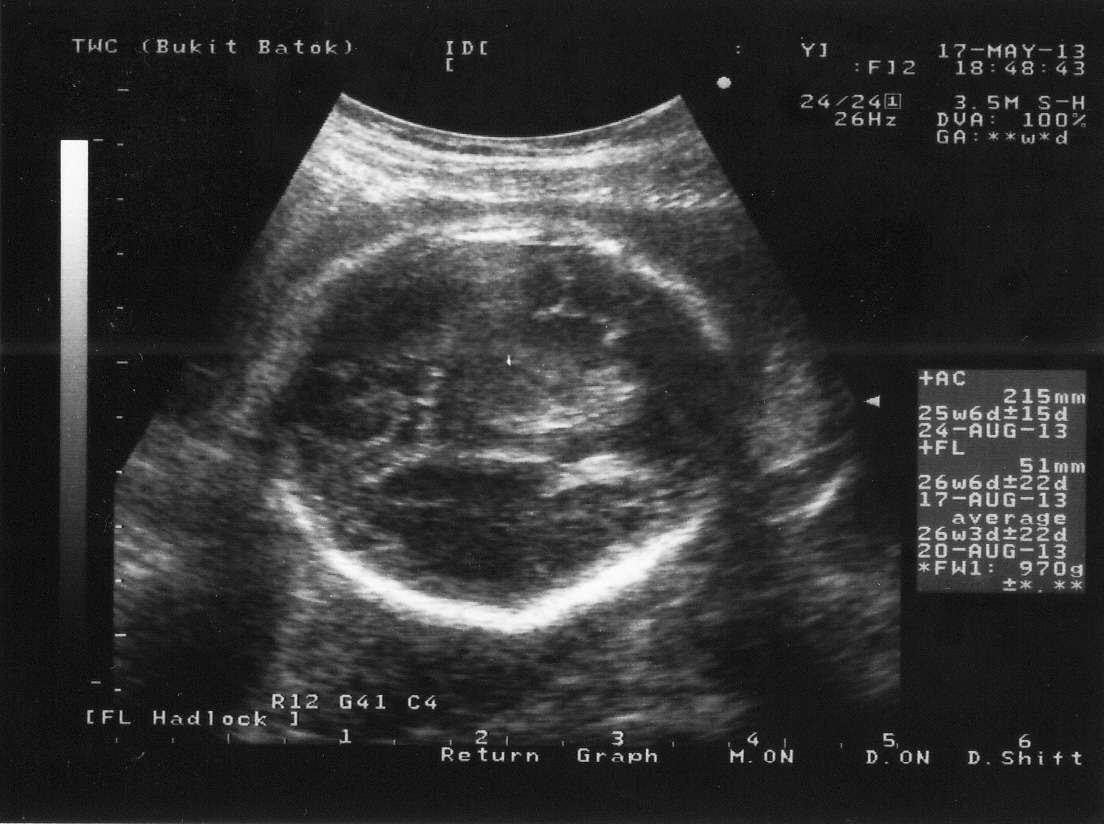

So far so good, everything's going well, the baby is actively moving day and night

The size is 970g, almost 1 kg which is the average of week 27 milestone